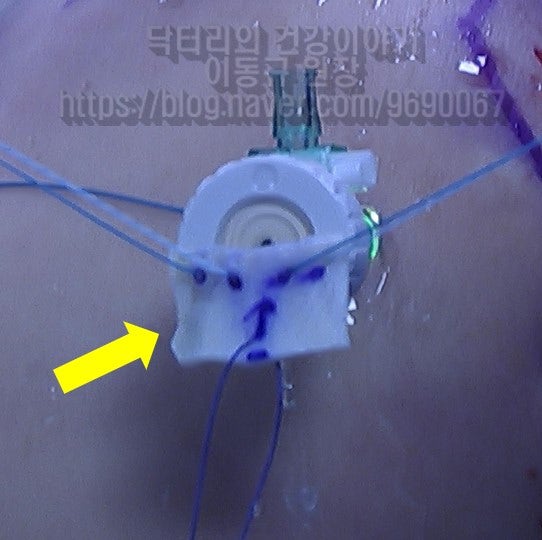

이 환자의 경우 나이가 비교적 젊음에도 불구하고 힘줄의 상태가 매우 좋지 않았습니다. 아마 수년간 통증주사(아마도 스테로이드)만 맞고 팔을 계속 사용하면서 회전근개 손상은 점점 진행되고 퇴행성 변화가 가속화 된 것으로 사료됩니다. 수술 후 6주에 MRI 검사를 시행하였습니다.